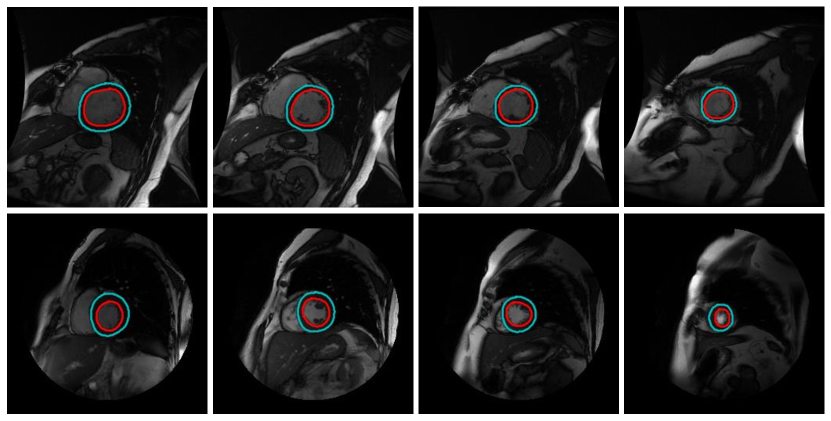

Good results: Selected prediction examples from the Sunnybrook test set are shown in Figure 8. As shown in the figure, our model is able to produce accurate results on most slices of left ventricular MRI.

Failure results: As shown in Figure 9, our model has difficulty in segmenting (a) left ventricle with ambiguous or imperceptible boundaries, and (b) the apex and basal regions.

![]() |